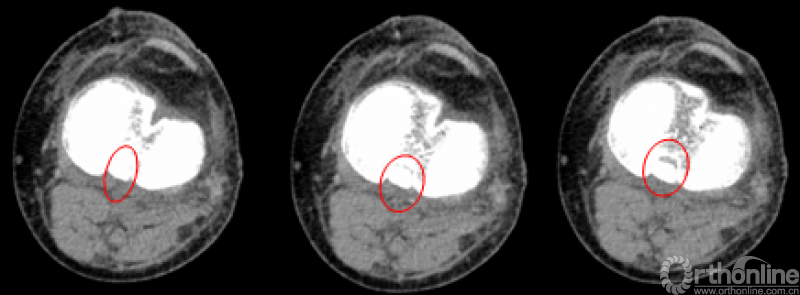

CT

MRI